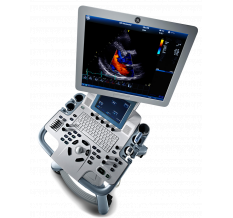

УЗИ аппарат Voluson S10 BT18

УЗИ-аппарат Voluson S10 был создан компанией General Electric для применения в гинекологии на основе уникальной инновационной технологии Core Architecture. Пакеты программ и аппаратные возможности сканера позволяют ему быть одним из лидеров в области диагностики различных заболеваний у женщин.

Voluson S10 помогает пациентам найти ответы, которые они ищут в моменты вашей практике. Построенный на архитектуре Voluson предоставляет исключительное качество изображения и улучшенный функционал наряду с широким перечнем приложений, помогающем уверенно принимать важные клинические решения и оставаться на пике достижений визуализации.

Улучшенная эргономика

Особенность системы Voluson S10 — это удовольствие от использования, наряду с дизайном, который инстинктивно ведет вашу руку для лучшего контроля. Вы можете работать сконцентрировавшись на изображении и пациенте, а не на меню и кнопках.

- 10 дюймовый тач-скрин монитор — упрощает рабочий процесс. Работать так же просто, как пользоваться планшетом.

- Однокнопочное управление для настройки и высоты и наклона панели.

- AutoTGS — быстрая настройка яркости и контраста изображения одним нажатием.

- 4 активных порта датчиков — больше датчиков готовых к применению без прерывания исследований.

- Жидкокристаллический дисплей, диагональ: 19 дюймов, развертка построчная, цветной

- Командный дисплей, диагональ: 10.1 дюйма